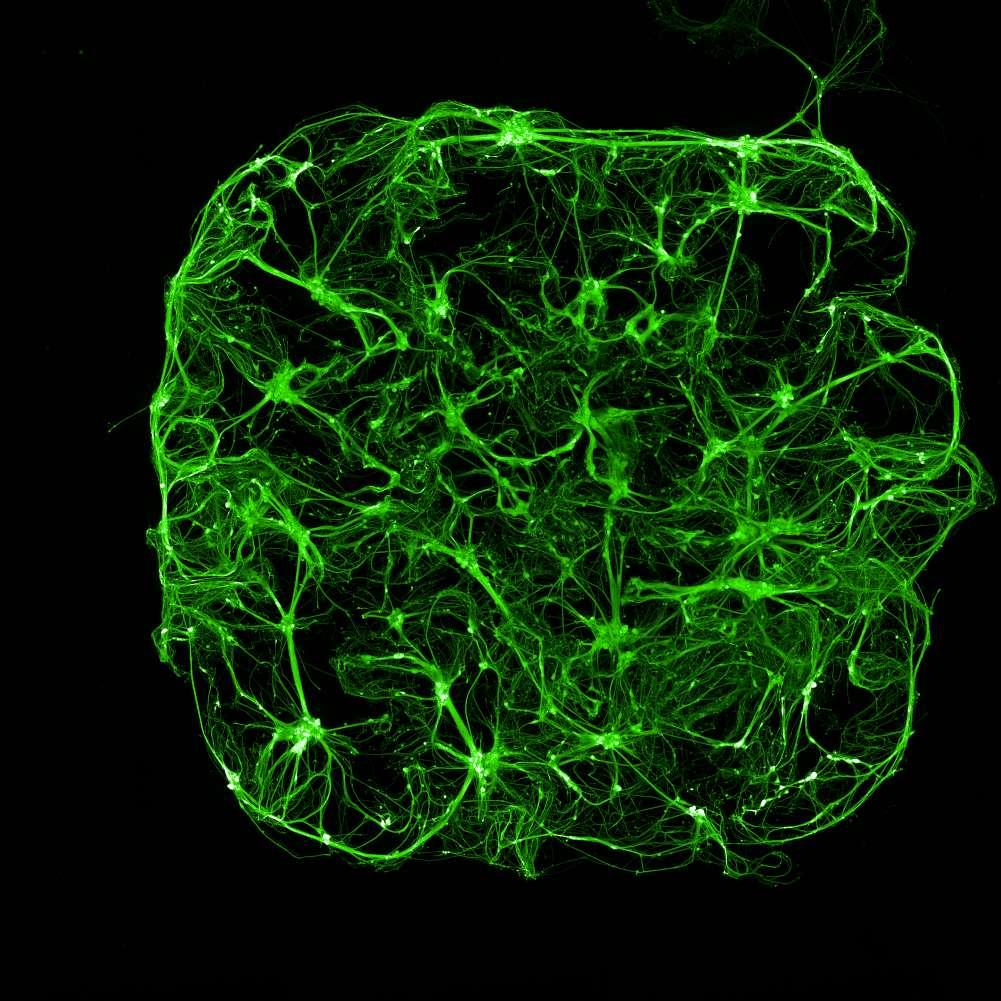

Calceinlabellingofneuron-astrocytecoculturesatmultipletimepointsshowedrobustcellviabilityandincreasedculturecomplexityovertime.

1week7weeks

Todistinguishneuronsfromastrocytes,co-culturesweretransducedwith NeuroLightlentivirus,encodinganmRubyfluorescentproteindrivenbythe synapsinpromoter.Theseresultsdemonstratethatthehydrogelmatrixisamenable toefficienttransductionbylentiviruses.